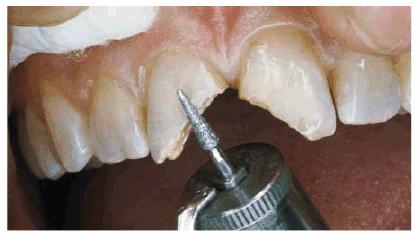

Figur 323s1823d e 18-3A: This young lady fractured her maxillary anterior incisors. Despite numerous bonding repairs, she continued to refracture the teeth. Because she also objected to the incisal translucency, she was treatment planned for three porcelain laminates.

Figur 323s1823d e 18-3B: The initial preparations for the

three porcelain laminates were done with a 0.5-mm depth cutter (Brasseler LVS

System, Brasseler,

Figur 323s1823d e 18-3C: The two-grit diamond is used to reduce the enamel to the predetermined depth cut.